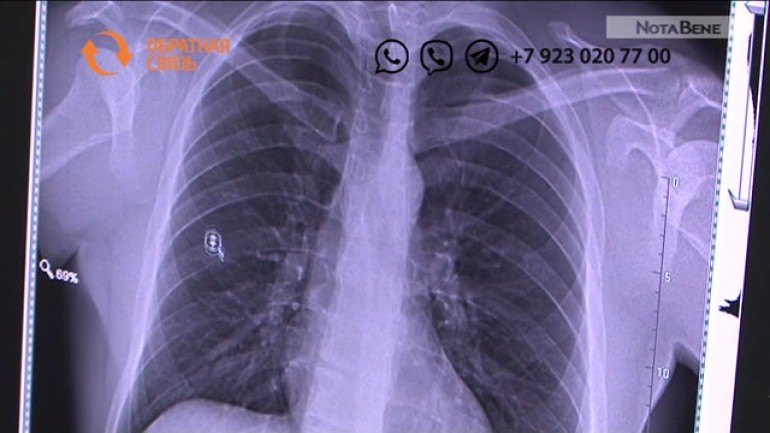

Фотографии рентгеновских снимков без необходимости направления от врача